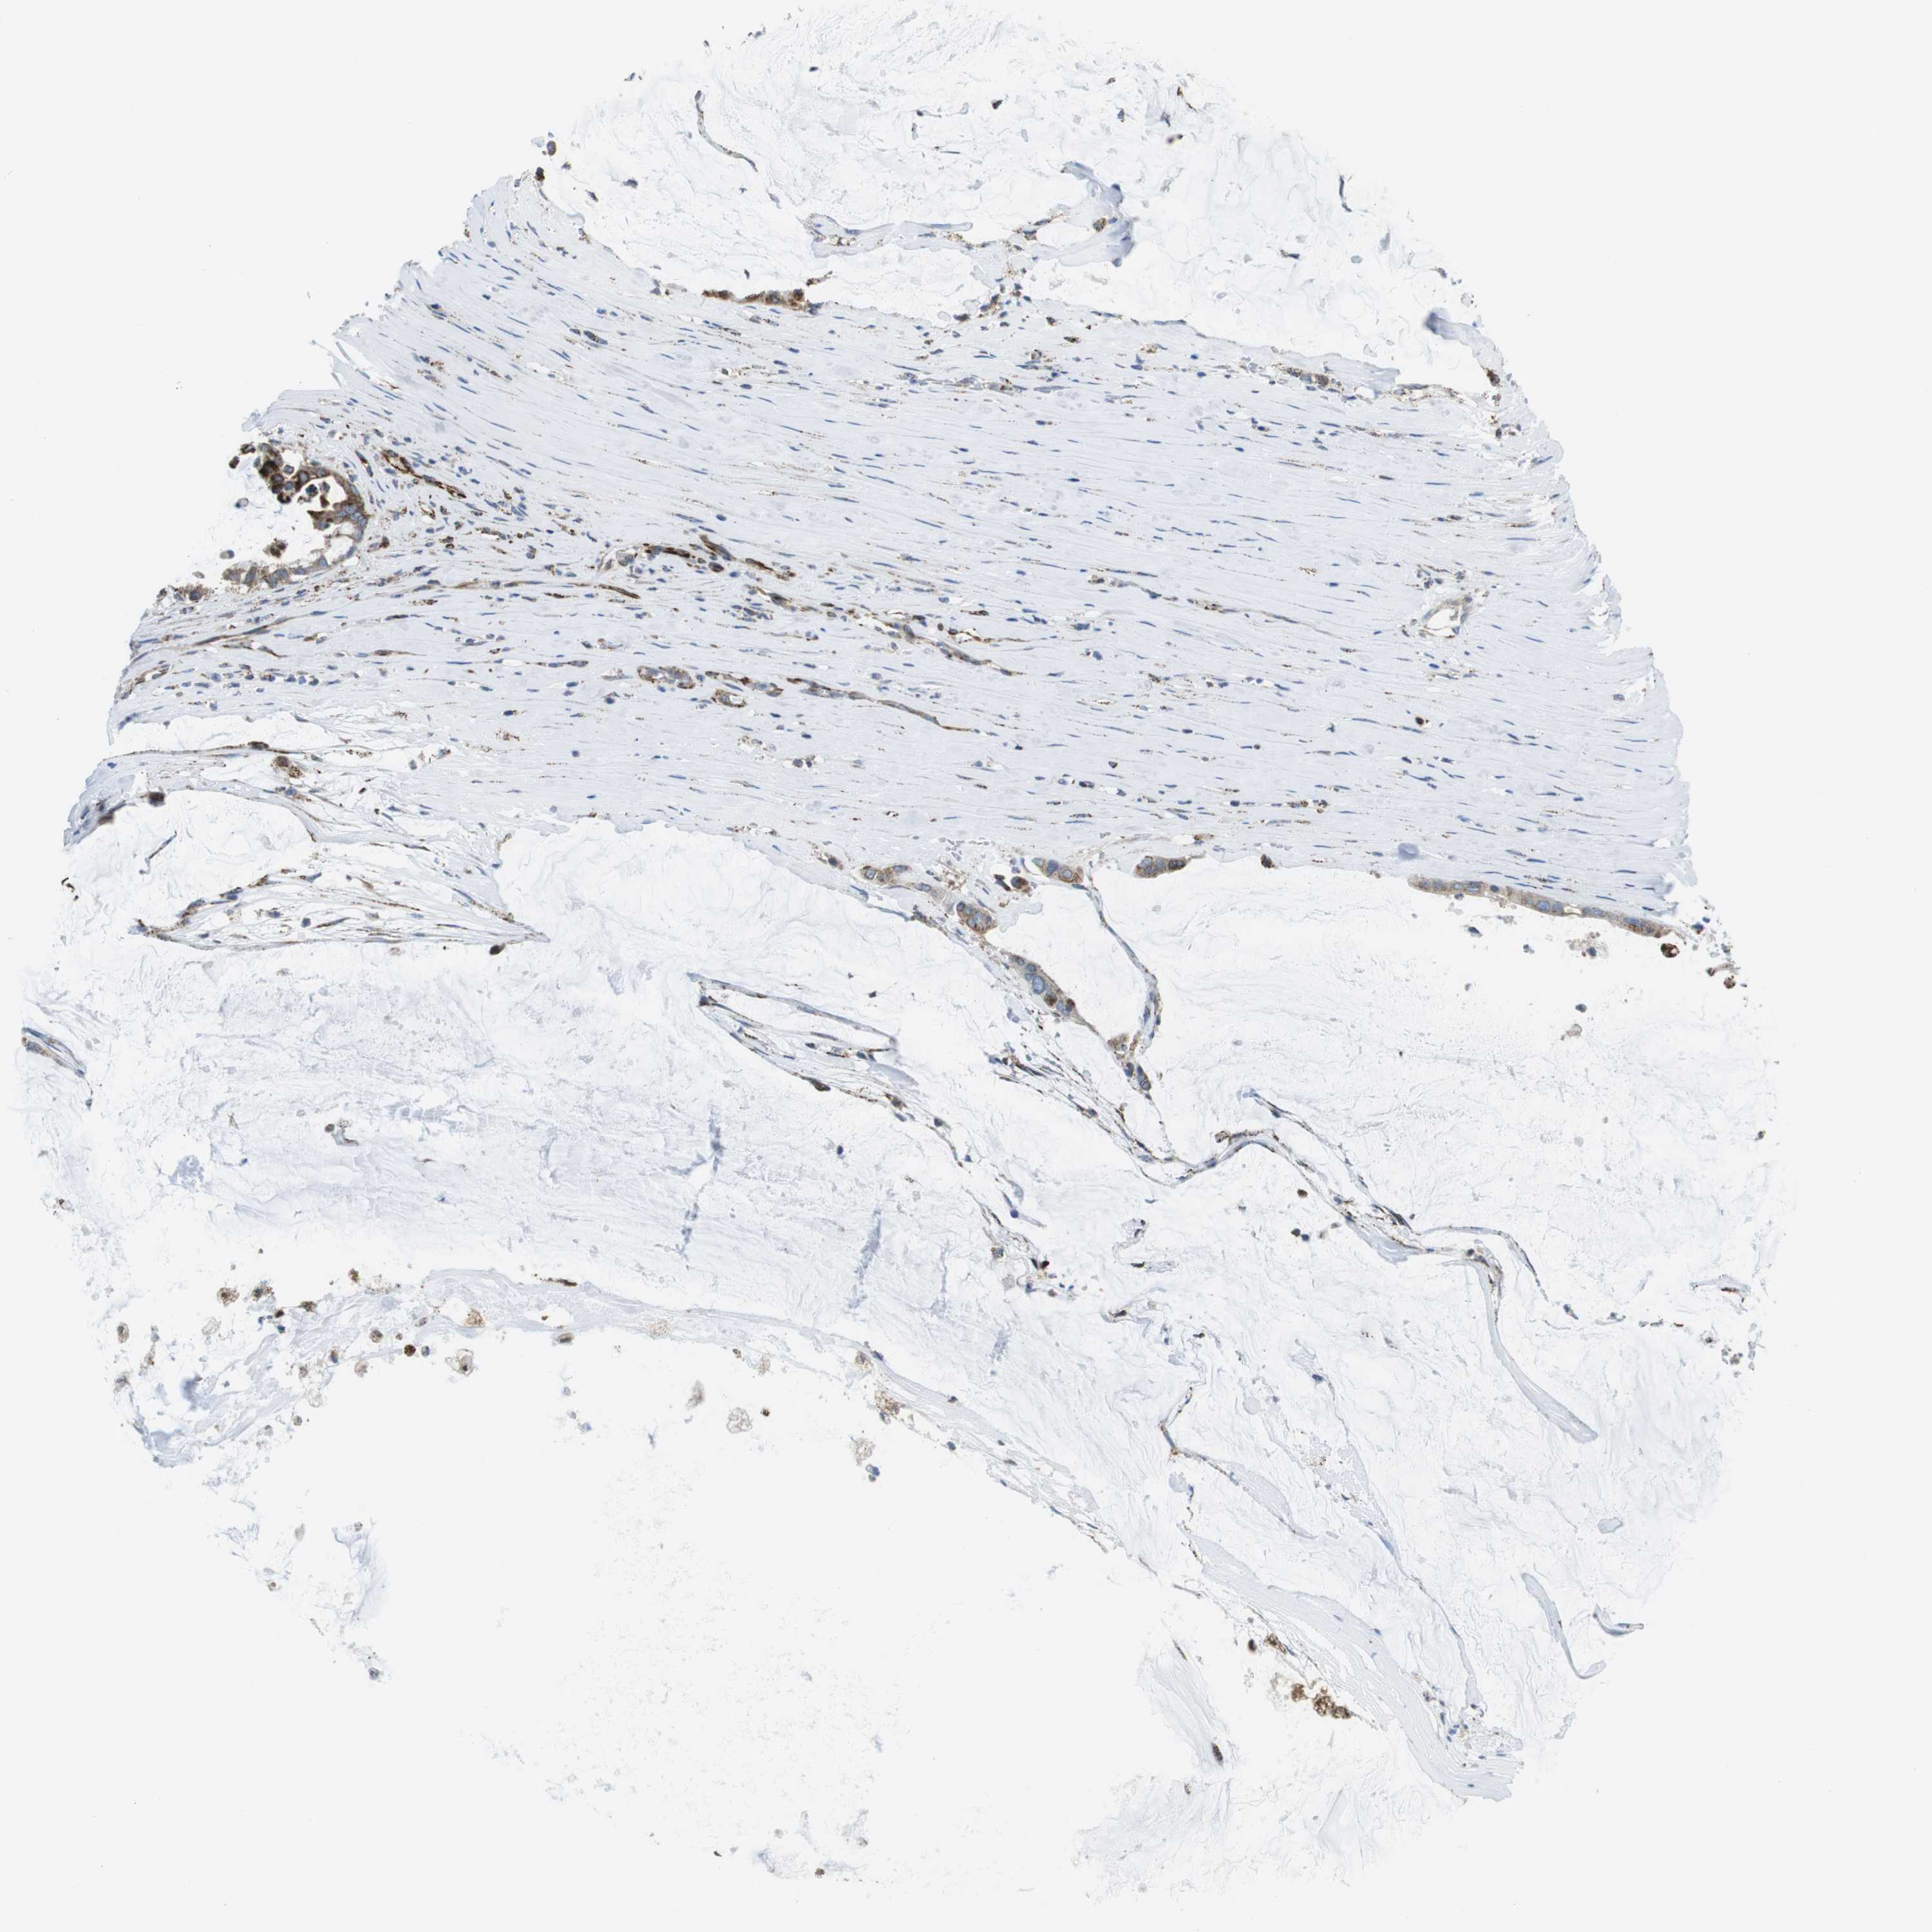

PANCREATIC CANCER - Protein expressioni

A mouse-over function shows sample information and annotation data. Click on an image to view it in a full screen mode. Samples can be filtered based on level of antibody staining by selecting one or several of the following categories: high, medium, low and not detected. The assay and annotation is described here.

Note that samples used for immunohistochemistry by the Human Protein Atlas do not correspond to samples in the TCGA dataset.

Antibody stainingi

Antibody staining in the annotated cell types in the current human tissue is reported as not detected, low, medium, or high, based on conventional immunohistochemistry profiling in selected tissues. This score is based on the combination of the staining intensity and fraction of stained cells.

Each image is clickable and will lead to virtual microscopy that enables deeper exploration of all samples and also displays staining intensity scores, fraction scores and subcellular localization as well as patient and tissue information for each sample.

Antibody HPA014849

Staining

High

Medium

Low

Not detected

Intensity

Strong

Moderate

Weak

Negative

Quantity

>75%

75%-25%

<25%

None

Location

Nuclear

Cytoplasmic/membranous

Cytoplasmic/membranous,nuclear

Adenocarcinoma, NOS